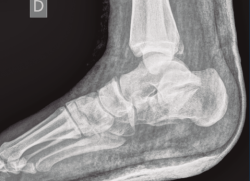

A su llegada a urgencias, se inmovilizó con férula posterior de yeso tras no conseguirse la reducción cerrada (Figuras 7 y 8). Debido a la patología asociada, subsidiaria de tratamiento quirúrgico de urgencias (artrodesis de L2 a L4 con tornillos transpediculares, por parte de neurocirugía), se decide demorar eñ tratamiento definitivo de la fractura luxación de calcáneo 2 semanas, hasta conseguir una mejoría en el estado de las partes blandas.

Figura 7. Radiografía lateral de pie y tobillo; se evidencia fractura de calcáneo y de maléolo tibial posterior.

Figura 8. Radiografía anteroposterior de tobillo, inclinación lateral del astrágalo, ocupación del espacio subperoneo, fractura maléolo peroneo y apertura de sindesmosis.